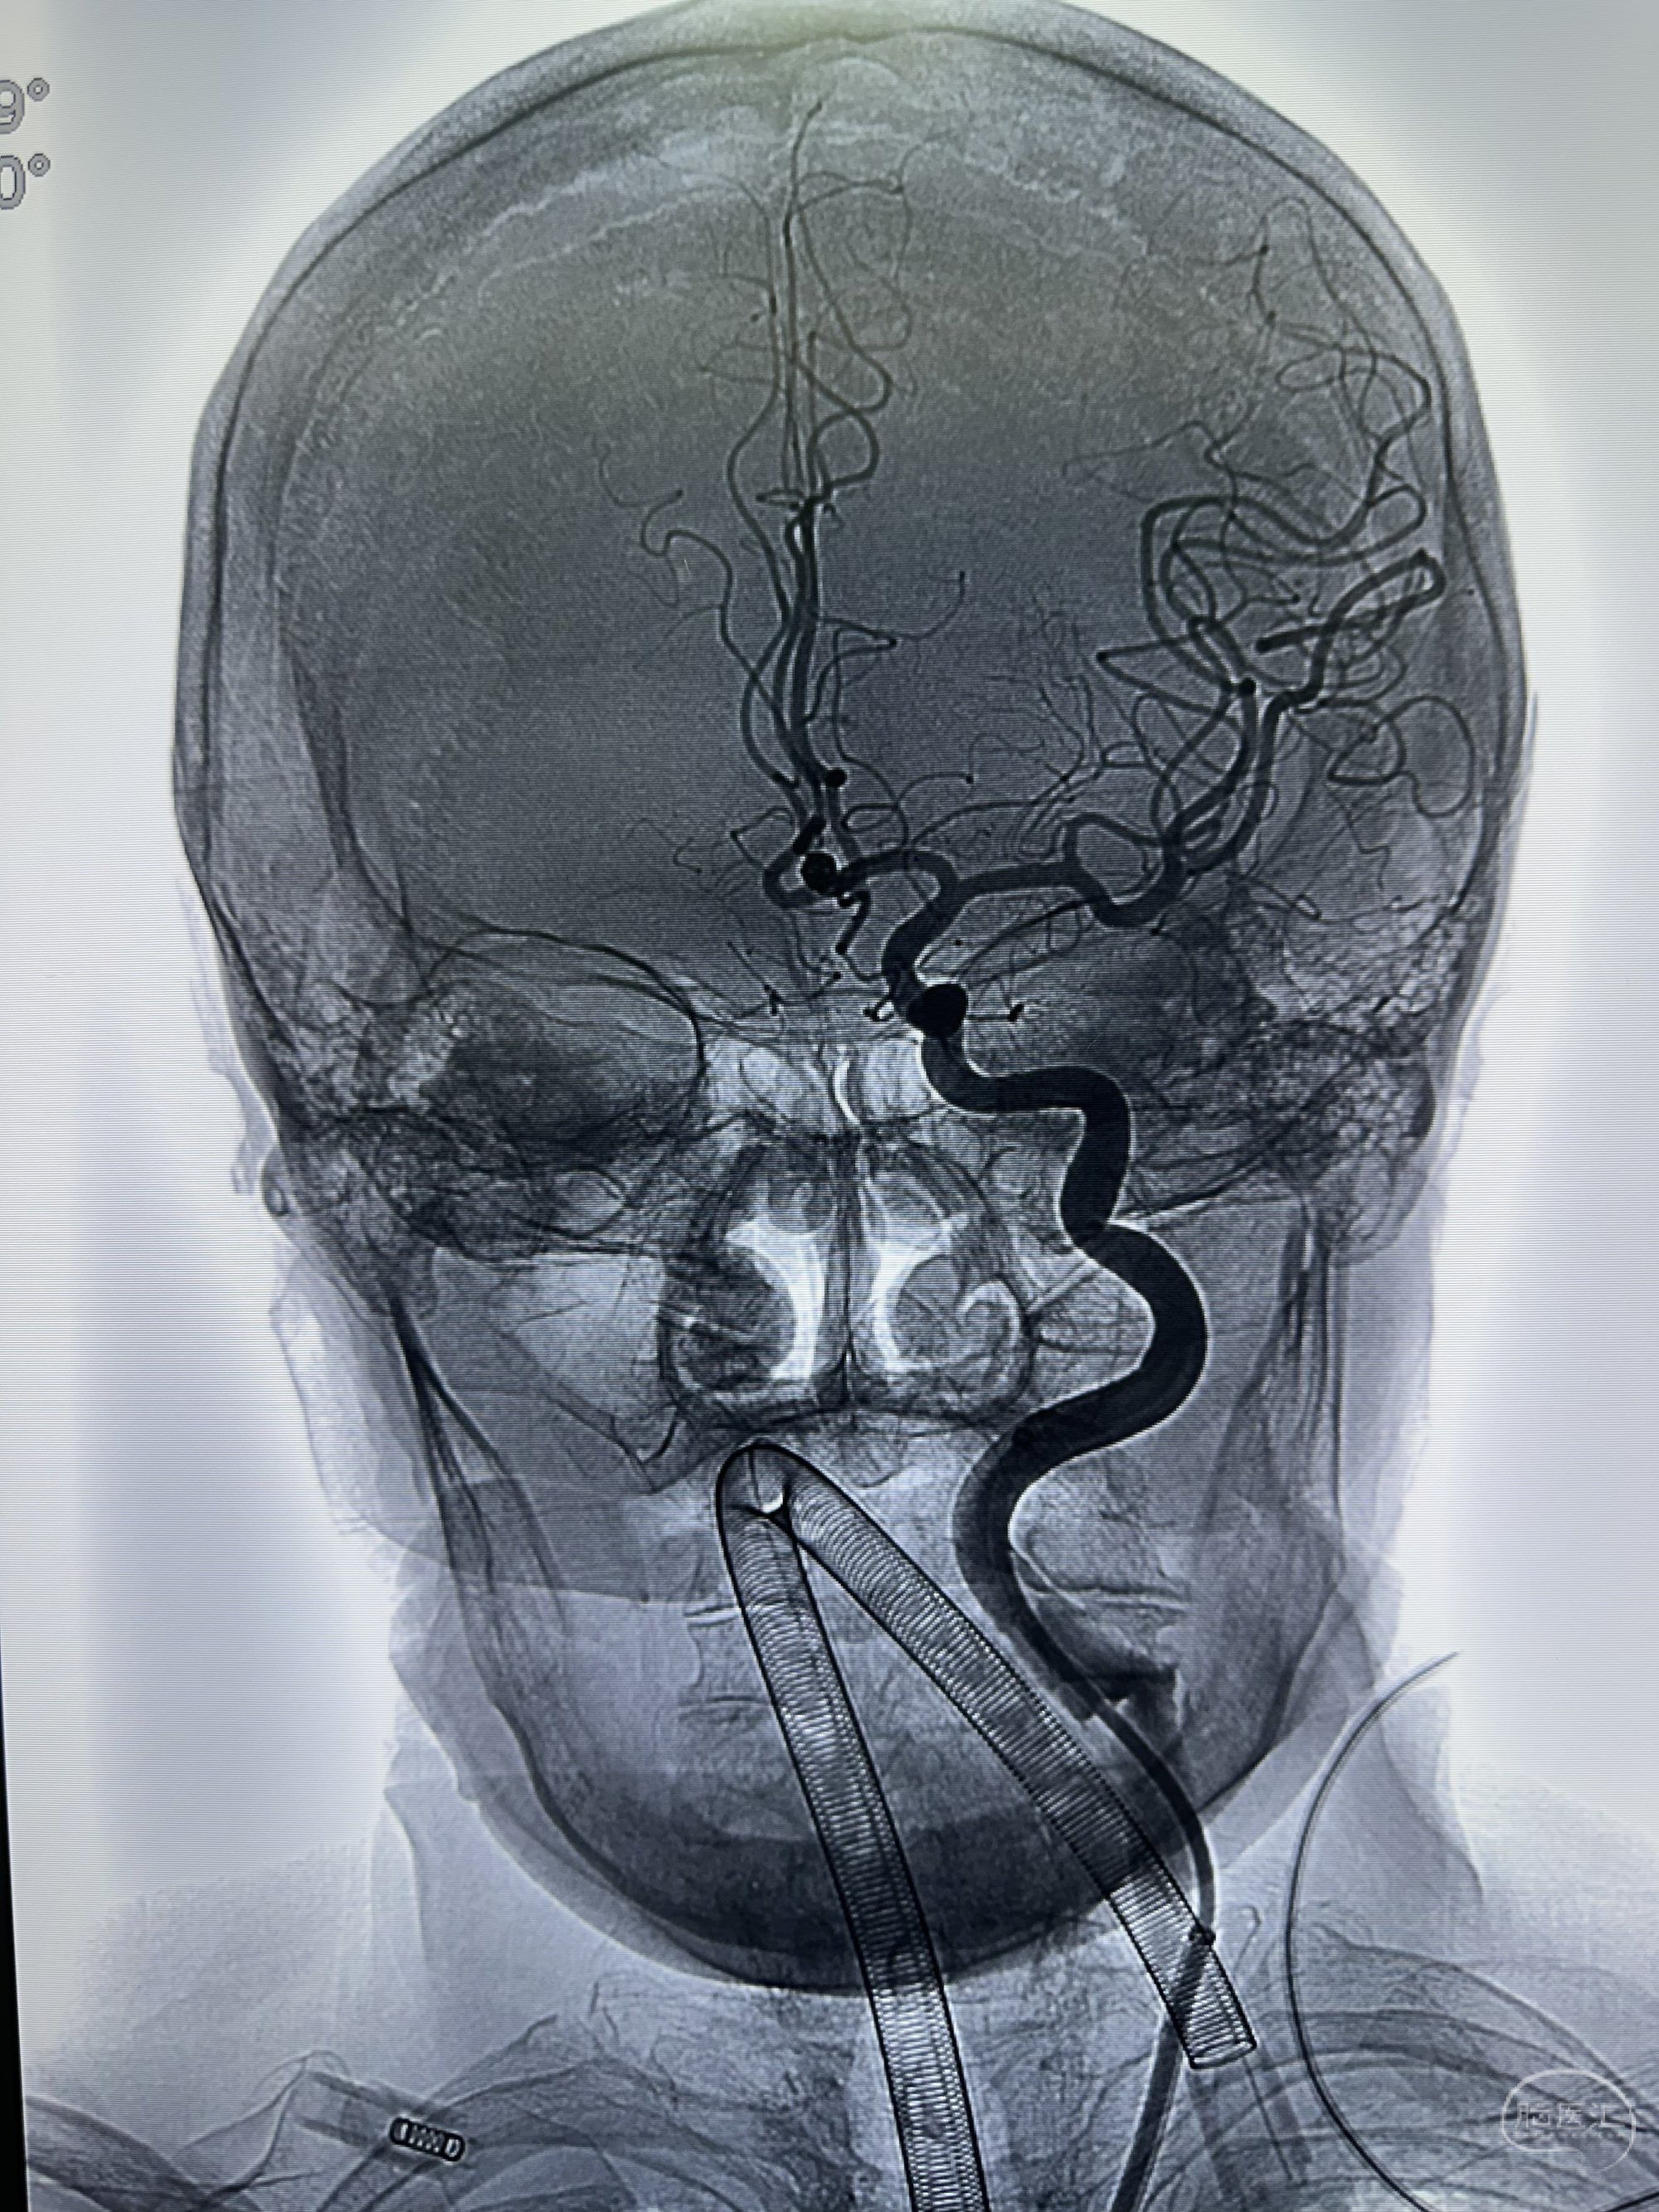

正位

骨窗

侧位